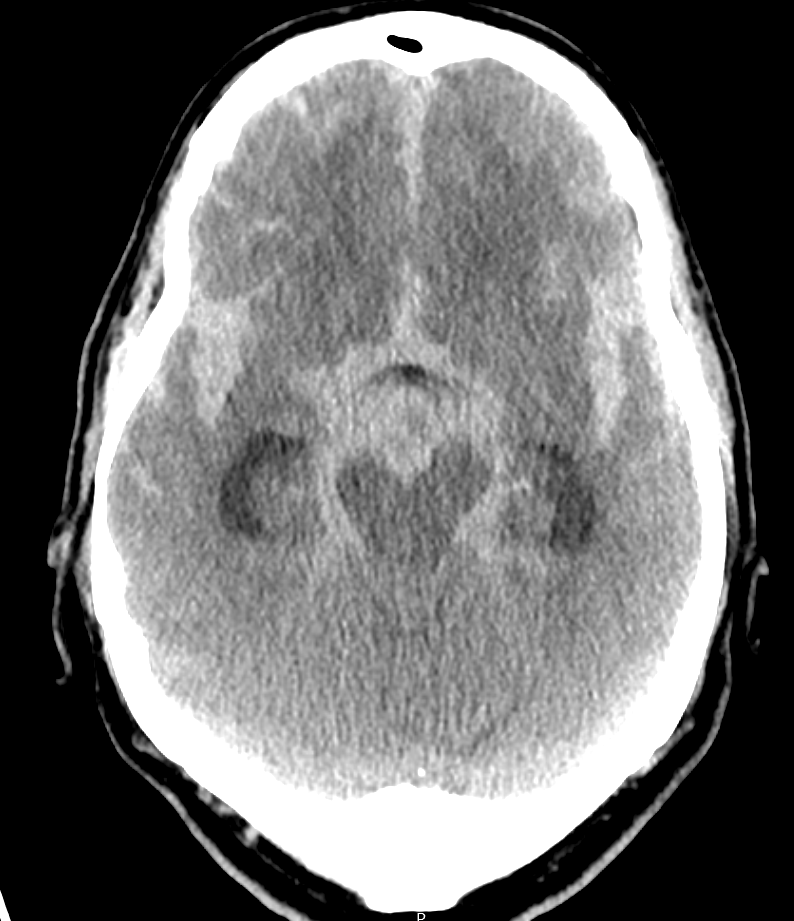

Subarachnoidalblutung mit hydrocephalem Aufstau im CT.

Ausgeprägte Subarachnoidalblutung im CT mit hydrocephalem Aufstau.

Subarachnoidalblutung CT

Axiales CT Bild eines Patienten mit einer ausgeprägten Subarachnoidalblutung und einem bereits vorhandenem Liquoraufstau.